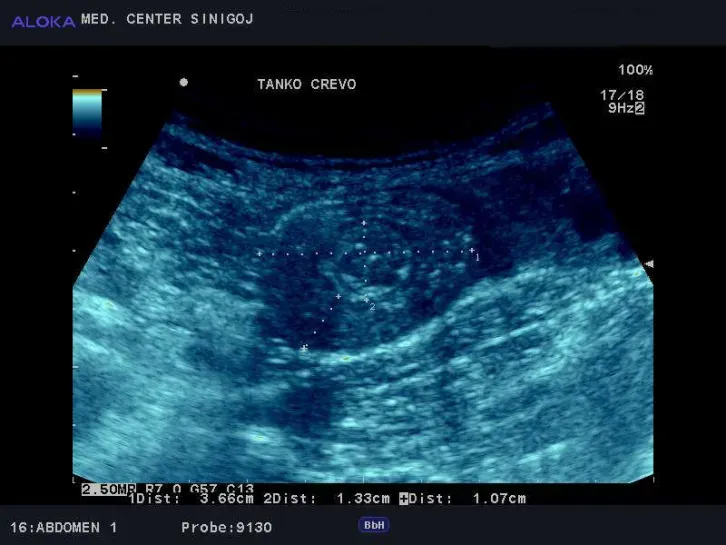

Predstavitev ultrazvok trebuha

Z ultrazvokom preiskujemo naslednje organe v trebuhu:

• jetra, žolčni vodi in žolčnik,

• trebušna slinavka in vranica,

• želodec, tanko in široko črevo,

• nadledvične žleze,

• retroperitonej,

• bezgavke,

• trebušne arterije (aorta, iliake, ledvične a., mezenterika, tr.celiacus),

• trebušne vene (v.cava, iliake, ledvične v., v.porte, v.lienalis, v. mez.).